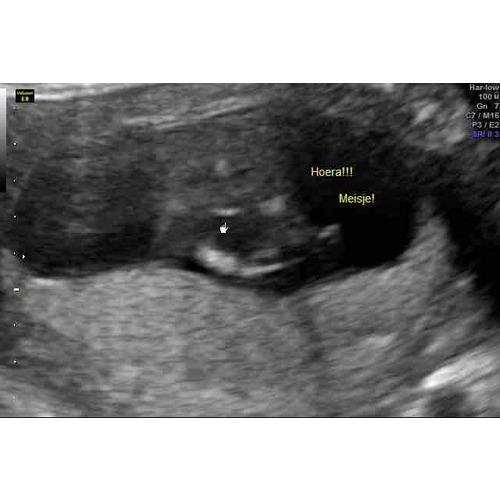

Hier de 3 streepjes bij 15 weken en 3 dagen